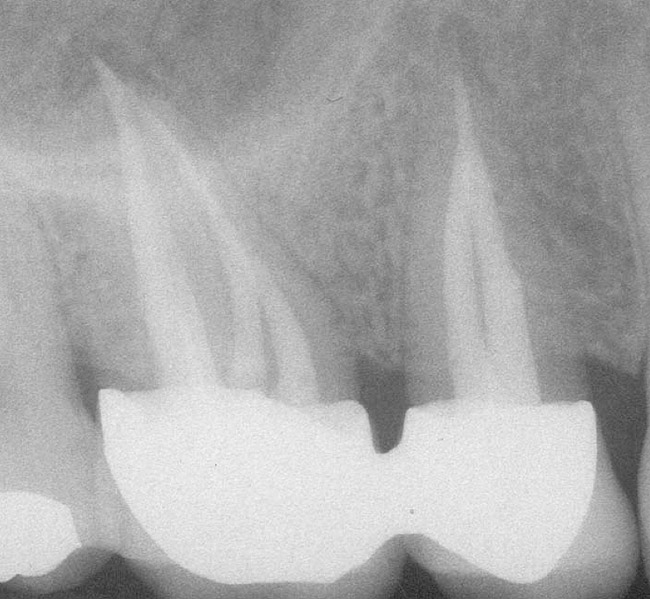

Figure 4a  Tooth No. 30 Nonsurgical root canal treatment had been completed 5 years before. The periapical radiograph revealed periradicular radiolucencies (periapical and in the furcation area).

Figure 4a

Figure 4e  The postoperative radiograph shows the re-treated tooth with 5 main canals.

Figure 4e

Figure 4f  The 1-year recall radiograph demonstrates the complete resolution of the periradicular radiolucencies.

Figure 4f